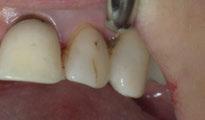

A partir del estudio radiológico y de las imágenes fotográficas podemos observar edentulismo de 17, 15, 14, 12,

Figura 1a. Foto intraoral frontal inicial.

Figura 1b. Foto intraoral lateral izquierda inicial.

Figura 1c. Foto intraoral lateral derecha inicial.

25, 26, 28, 37, 38, 47 y 48. Presentaba corona desajustada en 13 con extensión en 12, implantes en 35-36, 45-46, con coronas ferulizadas en 35-36, 45-46, y dientes anteriores superiores con enfermedad periodontal Grado IV.

2. Exploración de tejidos blandos

El paciente presentaba biotipo periodontal grueso, con márgenes asimétricos, con recesiones gingivales a nivel de 11 y 13 y pérdida de tejidos blandos interproximales.

3. Exploración de tejidos duros

En la exploración radiográfica (OPG, CBCT) observamos la existencia de pérdida ósea interproximal, lesión apical a nivel de la raíz mesial del 27 y el cordal del primer cuadrante incluido y neumatización sinusal del primer y segundo cuadrante.

En el CBCT observamos pérdida ósea posterior superior debida a la neumatización de los senos maxilares izquierdo y derecho. También podemos observar disponibilidad ósea apical suficiente en dientes antero-superiores para la realización de una Implantología inmediata y corticales vestibulares y palatinas conservadas.